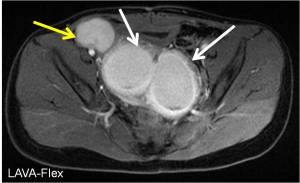

History: 13 year old female with pelvic pain

This is a case of a bicornuate uterus with hydrosalpinx of the right fallopian tube. Read about Imaging of Mullerian Duct Anomalies.